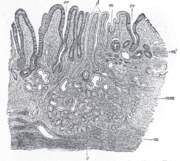

Žaludek

Žaludek (řecky gaster nebo stomachos; lat. ventriculus) je vakovitý, dutý orgán, který je součástí trávicí soustavy a jehož funkcí je mechanický (peristaltické pohyby) a chemický (enzymatická úprava) rozklad tráveniny. Dále zpracování, smíšení a promíchání potravy před jejím přesunem do střeva.

Stavba žaludku se může u různých druhů podstatně lišit. Rozeznáváme žaludky jednokomorové a vícekomorové, kde jsou vytvořeny předžaludky, jako například u skotu. Podle typu sliznice uvnitř samotného žaludku rozlišujeme žaludek jednoduchý a složitý. Složitý žaludek, jaký mají kůň nebo prase, má uvnitř dva typy sliznice – žláznatou a bezžláznatou. Jednoduchý žaludek masožravců a člověka je vyplněn pouze žláznatou sliznicí. Lidský žaludek je tedy jednokomorový jednoduchý žaludek.

Obecně lze říci, že býložravci mají mnohem složitější žaludek (vůbec celou trávicí soustavu) než masožravci.

U přežvýkavých živočichů se vlastní žaludek, jenž navazuje na předžaludky označuje jako slez (latinsky: abomasum). Stavbou se výrazně neliší od žaludku jiných druhů s jednoduchým žaludkem. U skotu má objem 10–20 litrů, u ovce a kozy 2–3 litry. Sliznice je žláznatá a produkuje pepsin a HCl, tvoří spirální řasy.

Má hruškovitý tvar. Sliznice produkuje žaludeční šťávy, které obsahují trávicí enzymy pepsin, chymosin, žaludeční lipázu a HCl.